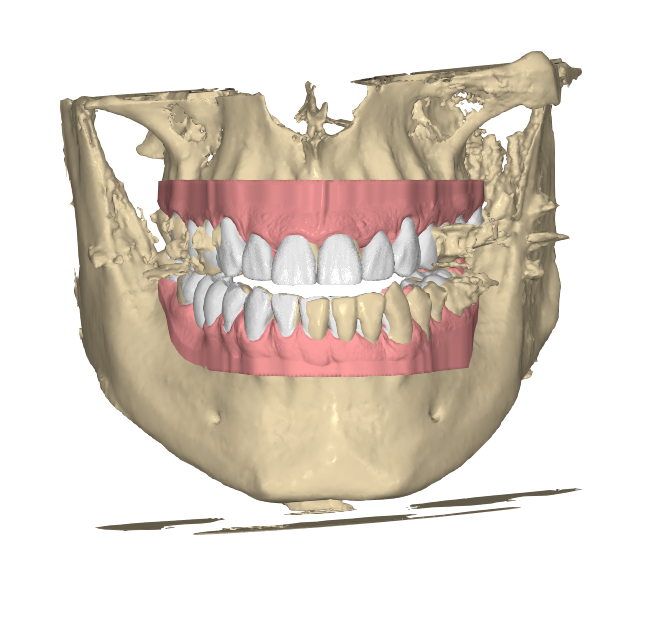

Entendemos que no siempre se dispone de archivos ideales. En Elevantia Solutions revisamos cuidadosamente cada caso, y en la mayoría de las situaciones tenemos dos opciones posibles:

A) Los archivos no son ideales, pero podemos trabajar con ellos: le informaremos de cualquier limitación, y aun así recibirá su diseño dentro del plazo establecido

B) No podemos trabajar con los archivos proporcionados: en Elevantia Solutions priorizamos la calidad y la excelencia en cada proyecto. Si las fotografías no cumplen con los requisitos, los archivos STL están incompletos o el registro de mordida es inexacto, no podremos proceder con el caso. Si esto ocurre, pausaremos el proceso, nos pondremos en contacto contigo y esperaremos archivos actualizados para continuar